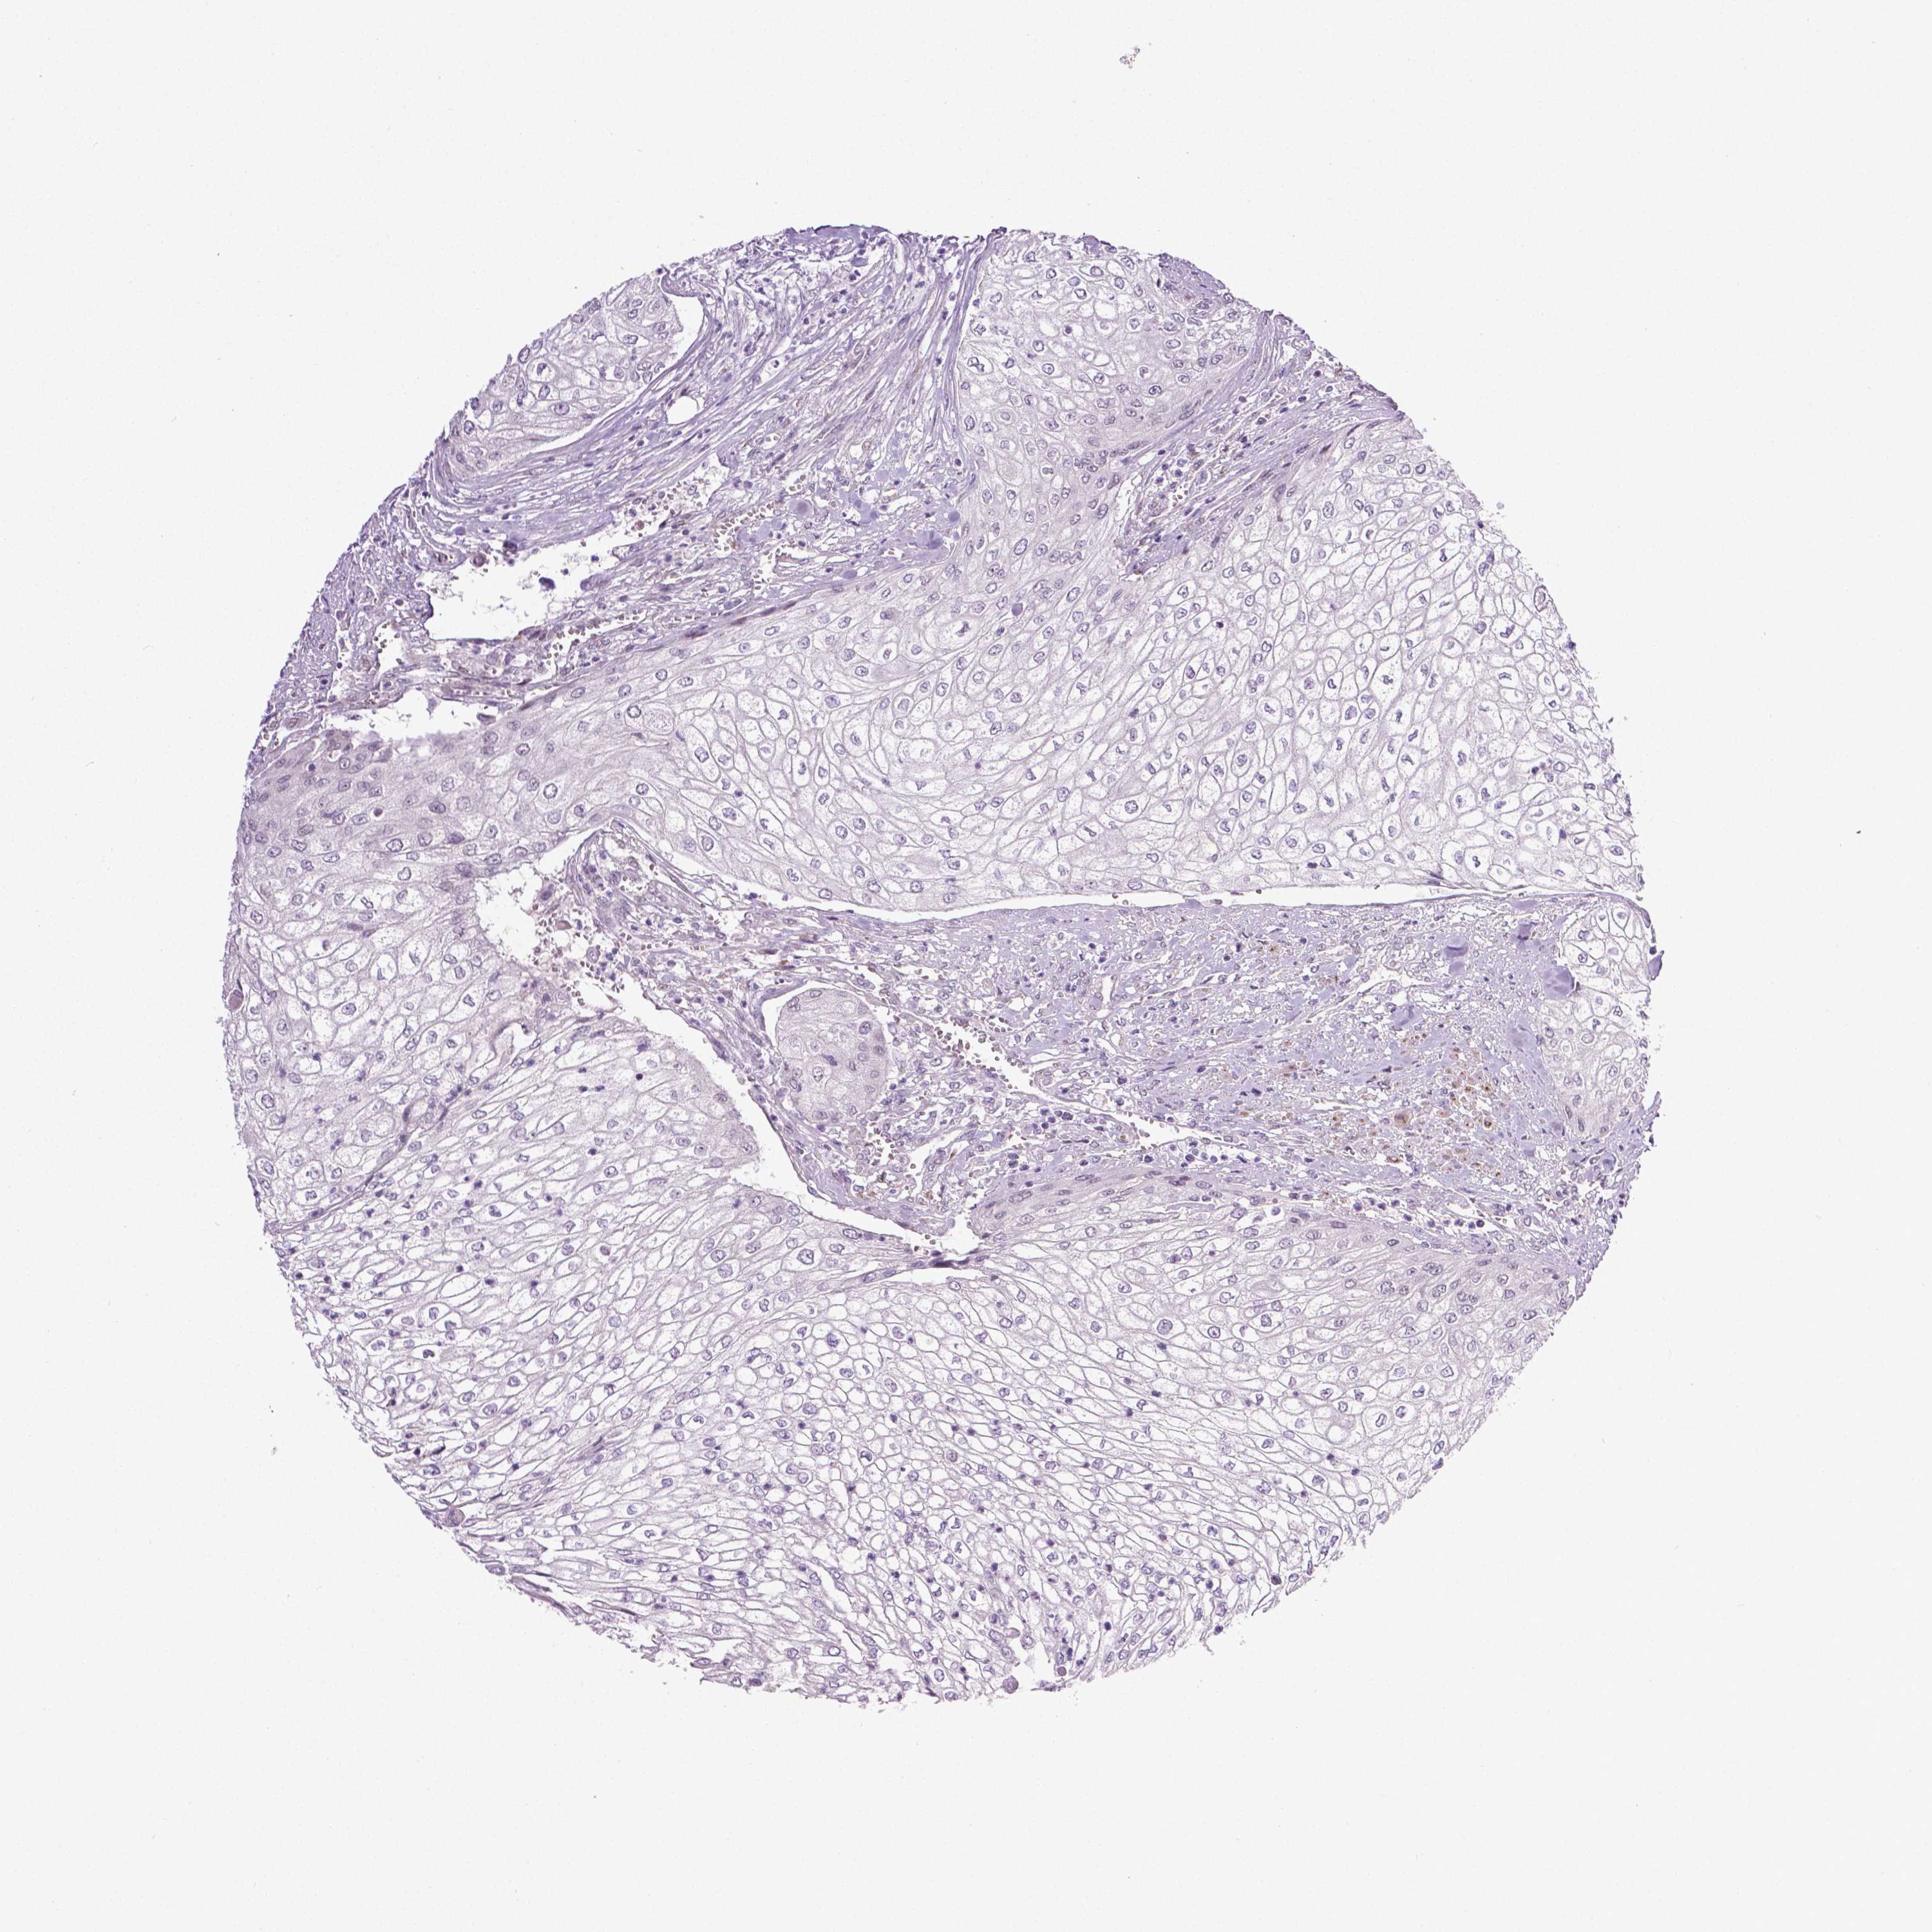

UROTHELIAL CANCER - Protein expressioni

A mouse-over function shows sample information and annotation data. Click on an image to view it in a full screen mode. Samples can be filtered based on level of antibody staining by selecting one or several of the following categories: high, medium, low and not detected. The assay and annotation is described here.

Note that samples used for immunohistochemistry by the Human Protein Atlas do not correspond to samples in the TCGA dataset.

Antibody stainingi

Antibody staining in the annotated cell types in the current human tissue is reported as not detected, low, medium, or high, based on conventional immunohistochemistry profiling in selected tissues. This score is based on the combination of the staining intensity and fraction of stained cells.

Each image is clickable and will lead to virtual microscopy that enables deeper exploration of all samples and also displays staining intensity scores, fraction scores and subcellular localization as well as patient and tissue information for each sample.

Antibody HPA010689

Staining

High

Medium

Low

Not detected

Intensity

Strong

Moderate

Weak

Negative

Quantity

>75%

75%-25%

<25%

None

Location

Nuclear

Cytoplasmic/membranous

Cytoplasmic/membranous,nuclear

Urothelial carcinoma, High grade

Urothelial carcinoma, NOS

Urothelial carcinoma, Low grade